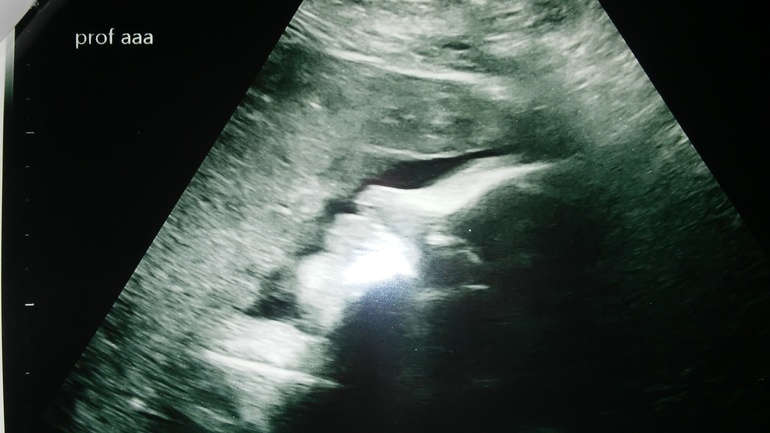

33 недели УЗИ

Фото личика девочки.